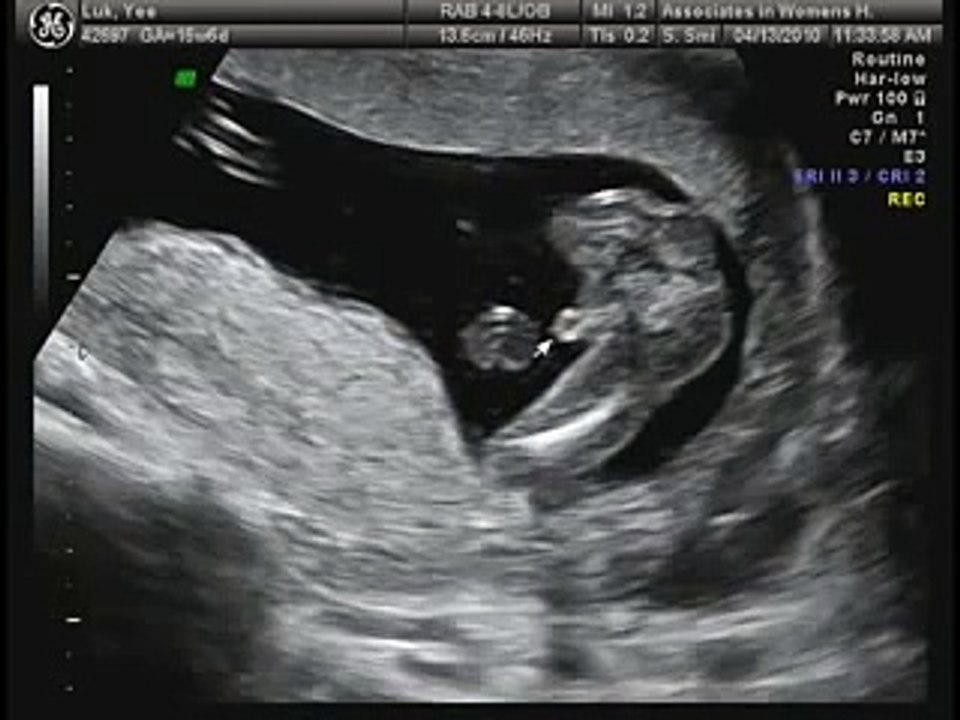

At the 8 week scan, your baby starts showing arms and legs, and sometimes you can even see movements during the ultrasound The black spaces on the baby's head are the brain still 8 weeks pregnant ultrasound boy or girl small medicine cabinet how to edit dark circles under eyes in photos booknet promo code24 week ultrasound, boy or girl??8 week ultrasound pictures boy or girl lace overlay for wedding dress / funny anime wallpaper 4k / funny anime wallpaper 4k

Normal 23 wees baby ultrasound Normal heart beat from 1 to 165 bpm If an ultrasound is needed at 23 weeks, then the protocol will definitely includes Fetal position ( vertex or breech) Doppler of the heart Measurements/fetal biometry if size discrepancies are presentFetal development at 29 weeks Your baby's heartbeat has become strong enough that you and/or your doctor can hear it clearly with a stethoscope A normal fetal heartbeat is 1 to 160 beats per minute and is pumping about 25 quarts of blood through your baby's body each day Baby's hearing continues to develop too, perhaps the baby isMy first ultrasound at 18 weeks 2 days pregnant We found out that we are having a baby boy!

What you can expect to see During the 16week scan, you can expect to see a baby that is fully formed but just very small But, if their development is on A midpregnancy (anatomy) ultrasound takes longer – about to 45 minutes – because the sonographer will look closely at your baby's basic anatomy, including the head, brain, face, neck, chest, heart, spine, stomach, kidneys, bladder, arms, legs, and umbilical cord so your provider can make sure they're developing properly 24 weeks pregnant ultrasound boyBaby development at 24 weeks Getting ready to breathe Respiratory sacs at the tips of the smallest branches of your baby's lungs are growing and multiplying, adding more surface area for the exchange of oxygen and carbon dioxide once your baby is born Still skinny, but not for longPicture of Second Trimester (24 Weeks) Second